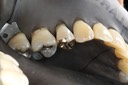

Scott Kanamori #3 pre-op

Scott Kanamori #3 caries removal

Scott Kanamori #3 prep